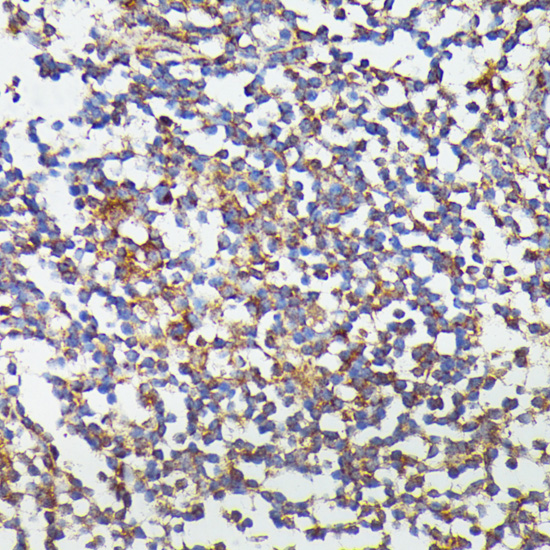

ApplicationWB, IHC; Recommended dilution: WB 1:500 - 1:1000, IHC 1:50 - 1:200